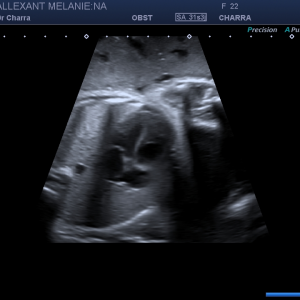

Diplômée en Echographie foetale et Gynécologique

Agrément National pour la réalisation des échographies du Premier Trimestre de grossesse

Membre du Collège d'Echographie Foetale Français (CFEF)